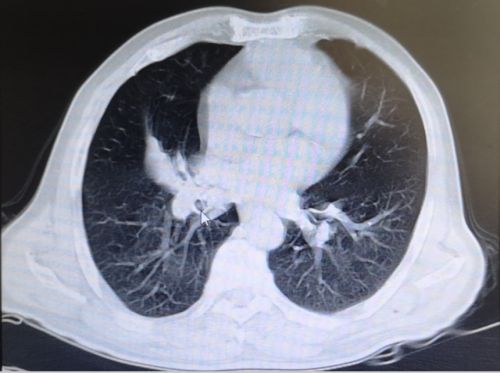

6月上旬,湖南宁乡75岁的姜爷爷连续4天发高烧,最高体温达到40.1℃,可自行退烧,除阵发性腹痛外没有其他不适。无规律的高热让平时身体硬朗的老人没了精气神,吃了几天中药不见好转,在家人的反复劝说下,来到捷克论坛 就诊。初步筛查排除新冠肺炎后,老年医学中心何翠娥副主任医师仔细询问病史,并为其进行详细的体格检查, CT 检查提示:1.右下肺阻塞性肺炎;2.右下肺团块灶,性质待定,考虑肿瘤可能性大。随即将其收入老年医学中心二病室,做进一步的检查和治疗。